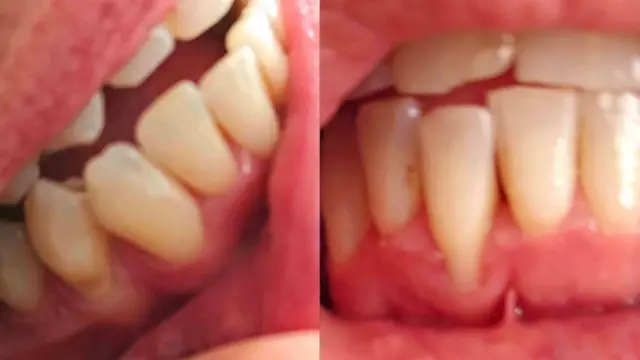

"Uno de mis dientes frontales se ha movido, mi esmalte se siente raro, como si los alineadores hubieran removido parte de él. Los alineadores han hecho que mi encía se reduzca lo que es una agonía".

Algunos de los factores que tienen en cuenta los dentistas para recomendar su uso es la salud de los tejidos duros y blandos de la boca, los dientes y las encías, así como si las raíces de los dientes pueden sostener un movimiento. Por eso es que las radiografías son fundamentales en este proceso.

Una vez que se empieza a llevar frenillos, las citas periódicas permiten a los dentistas controlar el movimiento de los dientes y detectar y tratar posibles complicaciones.

La odontóloga Victoria Sampson afirma que los usuarios pueden subestimar la fuerza que los alineadores ejercen sobre los dientes. Si no se detectan caries o enfermedades de las encías en una revisión física, se corre el riesgo de perder algunos dientes.

Dice que ha tratado a alguien que perdió un diente frontal después de usar los alineadores porque le movieron los dientes demasiado deprisa, desviando su mordida.

Las raíces de los dientes del paciente eran demasiado cortas para soportar la presión de los alineadores, lo que se habría detectado en una radiografía.